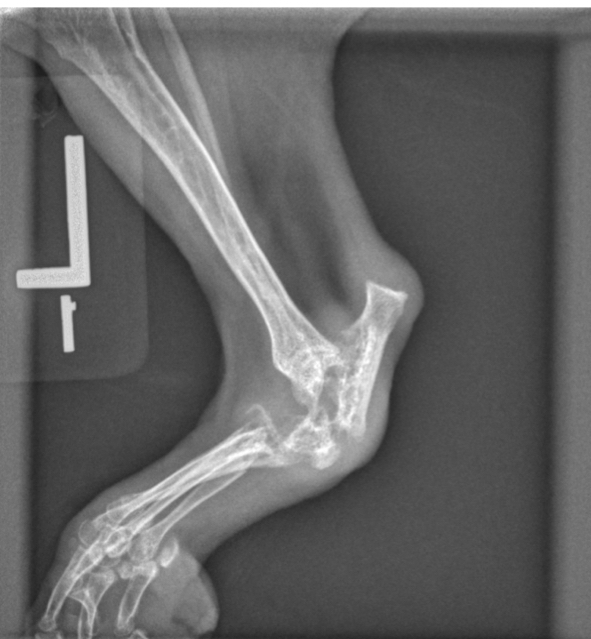

what wrong and is this monoarthrosis/itis or poly

1. Soft tissue swelling

2. Irregular epiphysis

3. Subluxation

Monoarthrosis/itis